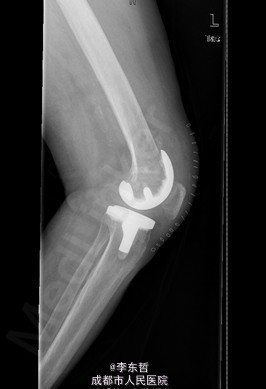

患者女,74岁,因“双膝疼痛20年,加重伴行走困难8年”入院。患者诉20年前开始出现双膝关节疼痛,负重行走、下楼时疼痛加重,休息后可缓解,尚可下蹲。自行购买止痛药口服,关节腔内注射玻璃酸钠、理疗等处理,疼痛时有缓解。但症状反复发作。8年前疼痛加重且行走困难,扶拐行走仅能坚持约10余米,上下楼梯艰难,下蹲不能,以左侧为重。遂来院就诊。

查体:跛行步态,双膝关节屈曲内翻畸形,双膝内侧间隙压痛,双膝髌股关节间隙压痛,左膝伸-20°,屈110°内翻10°。右膝伸-20°,屈110°内翻10°,双膝屈伸活动时髌骨下摩擦感(+)。 辅助检查:X片示双侧髌股关节内侧间室变窄,关节边缘骨赘增生,软骨下骨硬化。

入院诊断:1、左膝骨关节炎伴屈曲内翻畸形; 2、右膝骨关节炎伴屈曲内翻畸形; 诊疗计划:1、向患者及家属交待病情及注意事项。2、向上级医生汇报患者病情。3、完善相关术前检查;4、择期手术。